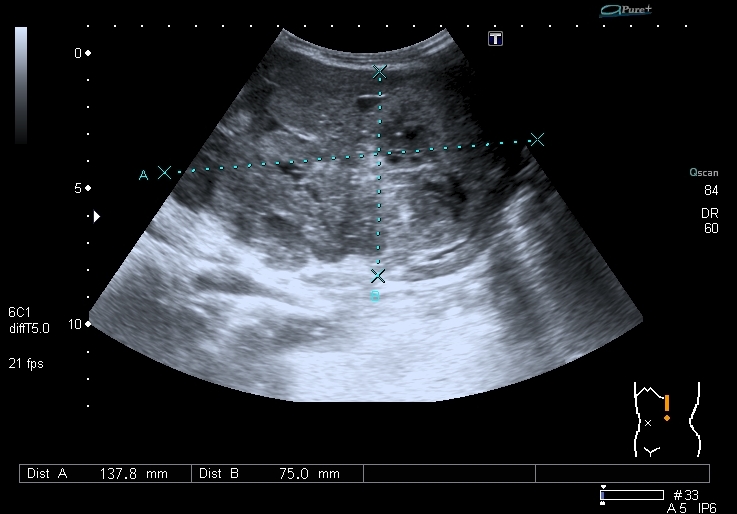

Предлагаю интересные изображения, полученные при сканировании лёгких через межрёберные промежутки и печень у ребёнка 4-х лет с подозрением на пневмонию

участок безвоздушной легочной ткани....похож на печень...пневмония в стадии опеченения... ;)

Согласен в отношении нижней доли правого лёгкого, изменения в ней похожи на сливную инфильтрацию при пневмонии, хотя носят несколько многоузловой характер. Но то что мы видим со спины в левом лёгком на пневмоническую инфильтрацию не похоже.

Добавляю сканы печени, я думаю они являются хорошей подсказкой о природе изменений в лёгких